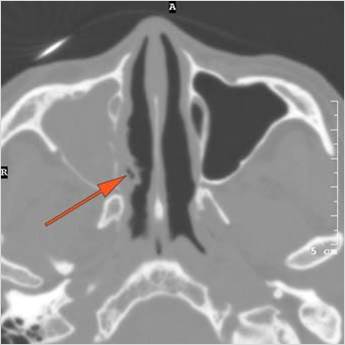

Nasal Cavity and Nasolacrimal Drainage System

There is mucoperiosteal thickening in the nasal cavity. [Yes/No]

There is ulceration or erosion of the nasal septum or turbinates. [Yes/No]

There is mucosal thickening of the posterior lateral walls of the nasal cavity, cribriform plate or the face of the sphenoid bone. [Yes/No]

There is infiltration of the fat surrounding the nasolacrimal sac. [Yes/No]

There is infiltration of soft tissues or bone erosion along the nasolacrimal fossa or canal. [Yes/No]